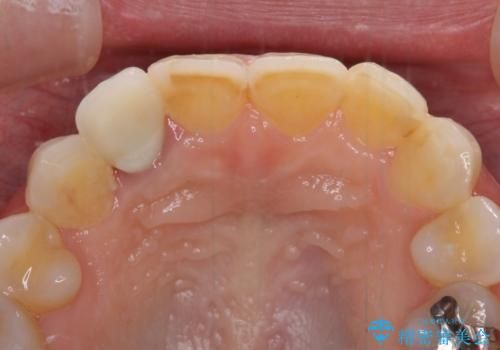

元々磨き残しによる歯肉の腫脹がありましたが、クラウンが歯肉深くに装着されていたため、特に腫脹が目立っていました。

仮歯に置き換えた際に歯周外科処置を行い、歯肉の腫脹が落ち着いたことを確認してオールセラミッククラウンにて補綴することとしました。